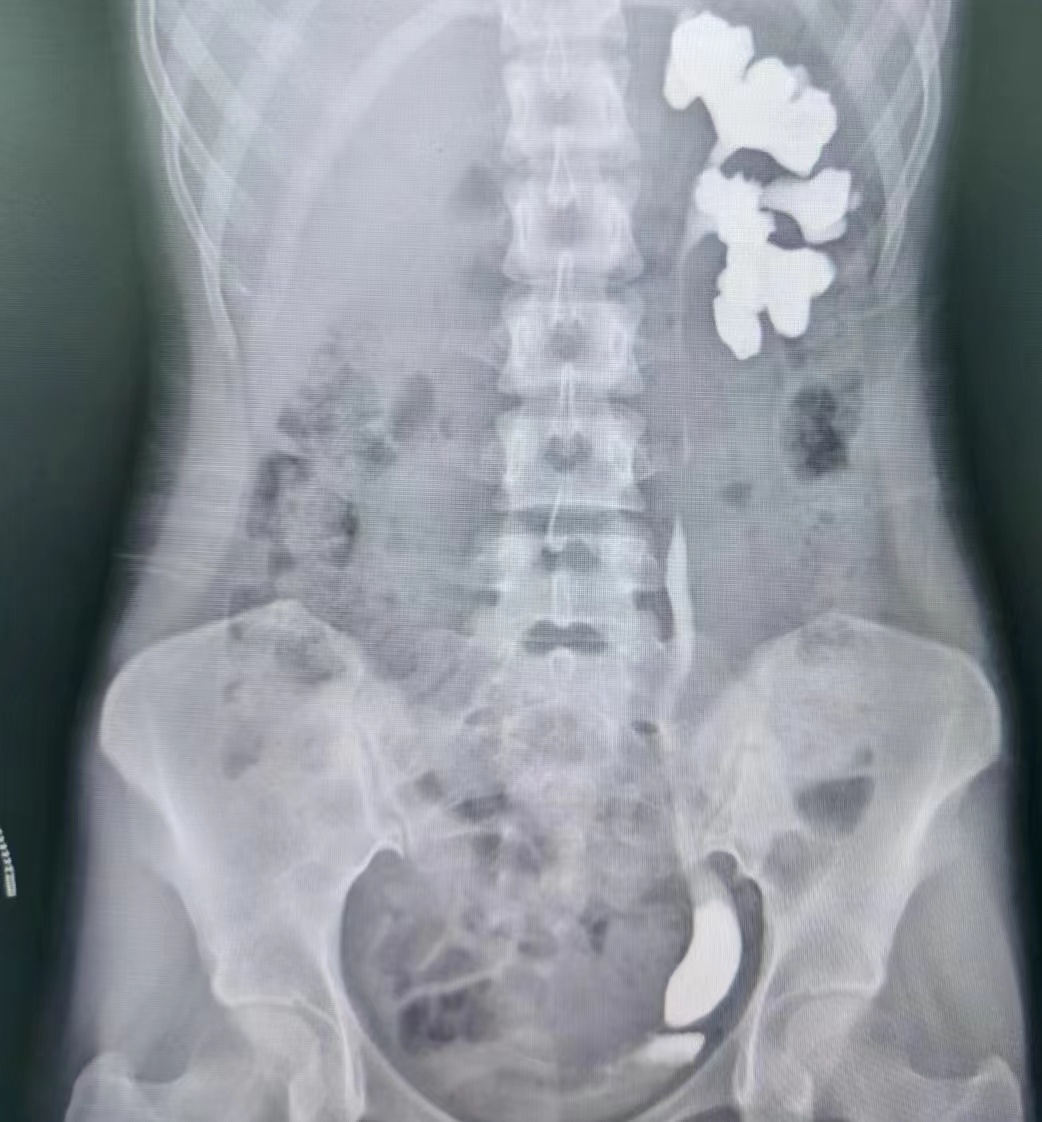

蔡高飞主任医师和王增利副主任医师诊疗组将患者收住入院,入院后行静脉肾盂造影和逆行肾虚输尿管造影提示左侧输尿管末端狭窄。科主任赵卫红立即组织全科讨论,由于输尿管下段走行毗邻髂血管和子宫动脉和卵巢、输卵管,术中稍有不慎损伤髂血管则会引起大出血,损伤子宫附件则会影响生育功能。考虑到患者年龄较小,本着手术效果和术后美观的原则,根据本科室近年来在腹腔镜手术方面的积累,决定为其实施腹腔镜下输尿管再植术,此手术方式创伤小,出血少,术中视野好,术后恢复快。

与患者和家属就治疗方案达成一致后,在赵卫红主任、蔡高飞主任医师现场指导下,由王增利副主任医师主刀,王明主治医师配合,为患者进行了“腹腔镜下输尿管再植手术”。手术共用时40分钟,过程顺利,术中出血量仅20ml。术后经过孙娟丽护士长快速康复护理团队的精细护理,患者身体迅速恢复,相关术后指标无明显异常,已于近日出院。